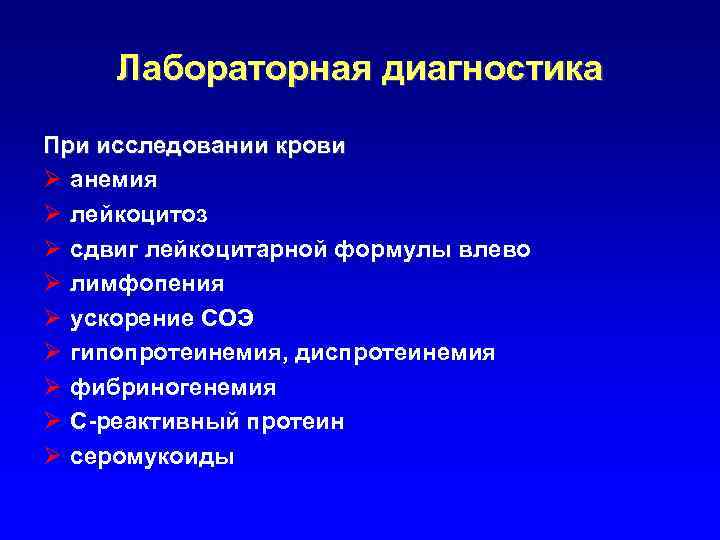

Лабораторная диагностика При исследовании крови Ø анемия Ø лейкоцитоз Ø сдвиг лейкоцитарной формулы влево Ø лимфопения Ø ускорение СОЭ Ø гипопротеинемия, диспротеинемия Ø фибриногенемия Ø C-реактивный протеин Ø серомукоиды